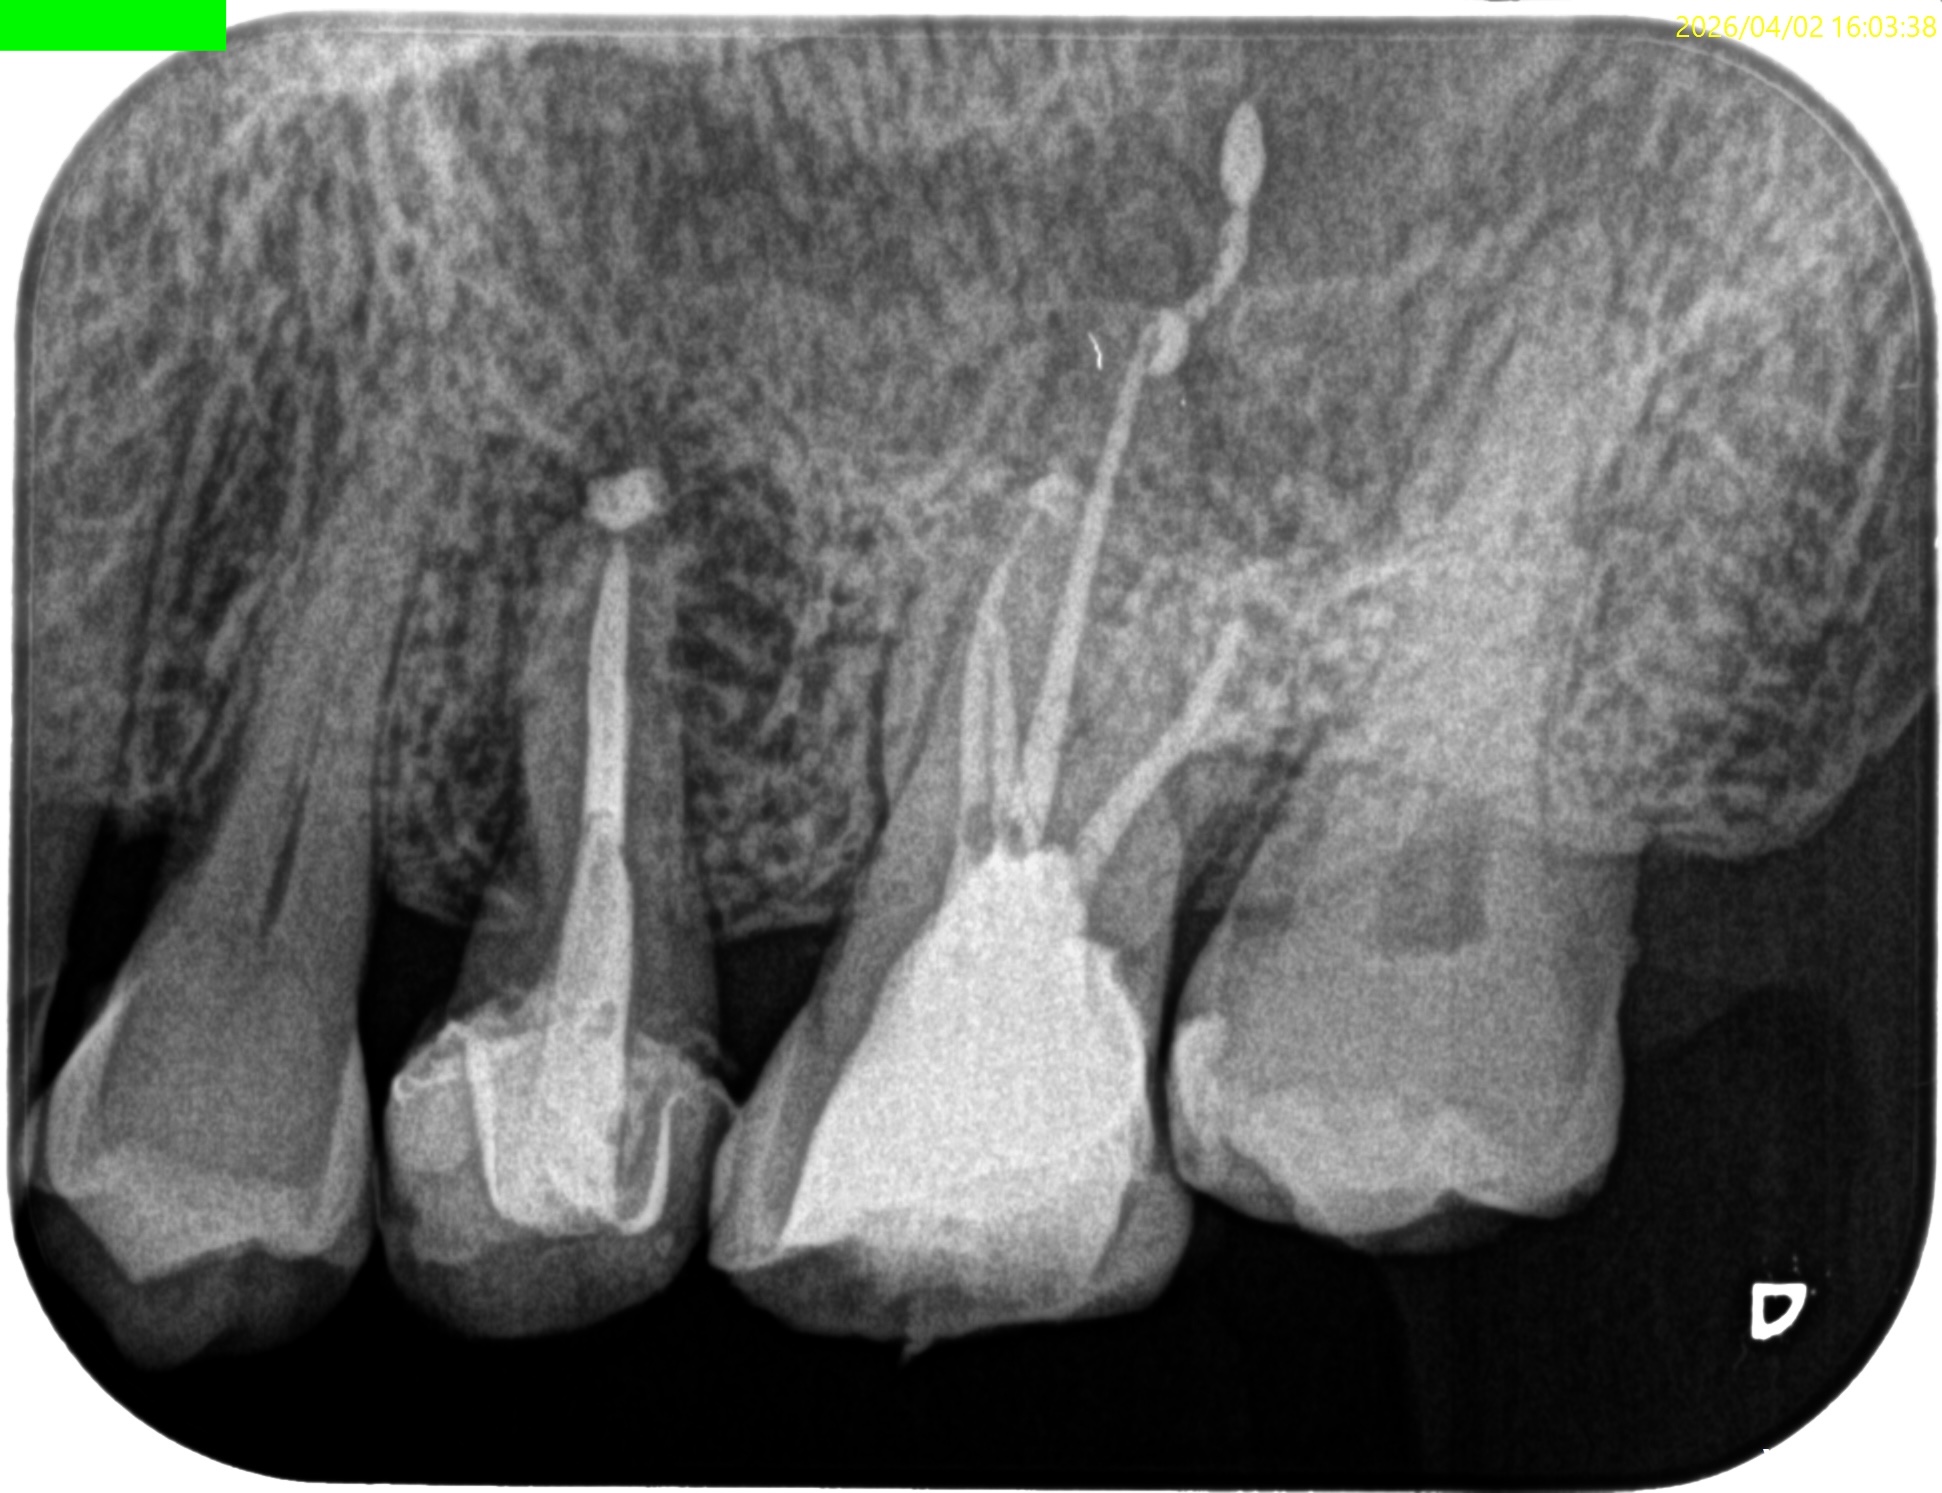

患者さんにいただいたレントゲンは以下である。

画質の悪いパノラマ写真だ。

これで根管の何を判断できるというのだろうか?

私には皆目見当がつかない。

Pre-op Endo test(2026.4.2)

このPA2枚でみても、東京の歯科医院の担当者は根管口さえ発見していないという臨床的事実がわかる。